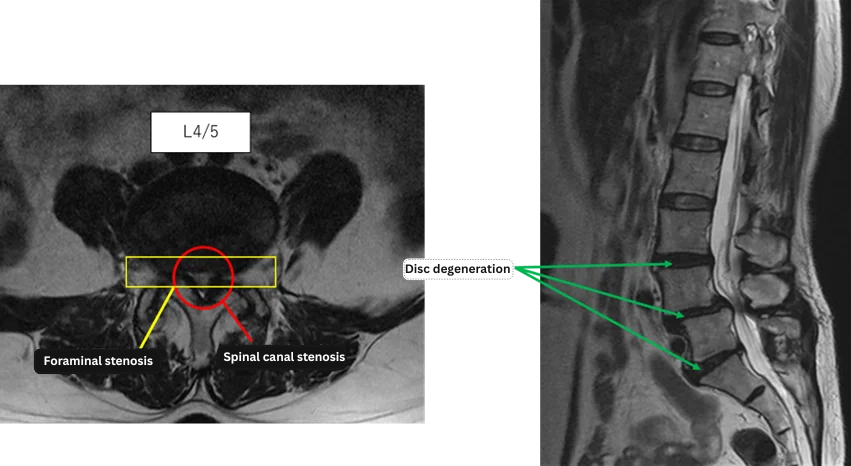

Imaging and findings

L1/2: No anomaly

L2/3: No anomaly

L3/4: Disc degeneration

L4/5: Disc degeneration, spinal canal stenosis, foraminal stenosis

L5/S: Disc degeneration, annular tear

The above findings were also observed on the imaging.

Disc degeneration at L3/4, L4/5, and L5/S, in addition to spinal canal stenosis, foraminal stenosis, and annular tear, were considered highly likely to be responsible for the patient’s primary symptoms.